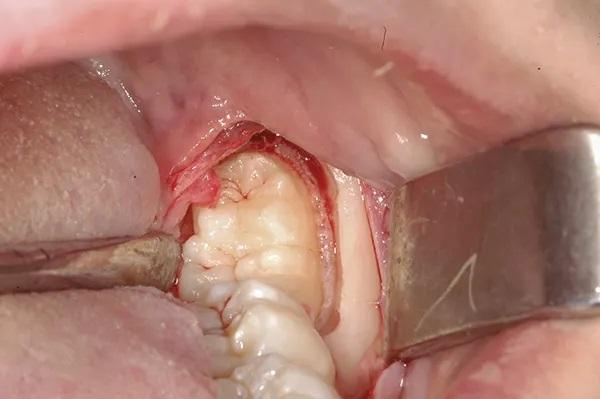

Пациенту было рекомендовано перед операцией использовать 0,12%-ный раствор хлоргексидина глюконата для полоскания рта. Была проведена местная анестезия с помощью блокады НАН и длинного щечного нерва с использованием двух картриджей с 3%-ным мепивакаином и сосудосуживающим средством, и была подтверждена глубокая местная анестезия. Был сделан разрез борозды от дистальной части зуба 3.6 до дистальной части зуба 3.7, при этом разрез гребня продолжался кзади от восходящей ветви нижней челюсти, и был поднят полнослойный конвертный лоскут. В частности, дистальный разрез продолжался под углом 45 градусов от дистобуккального бугорка зуба 3.7 до ветви нижней челюсти (Фото 3).

Фото 3: Окклюзионный вид “двойного зуба”.